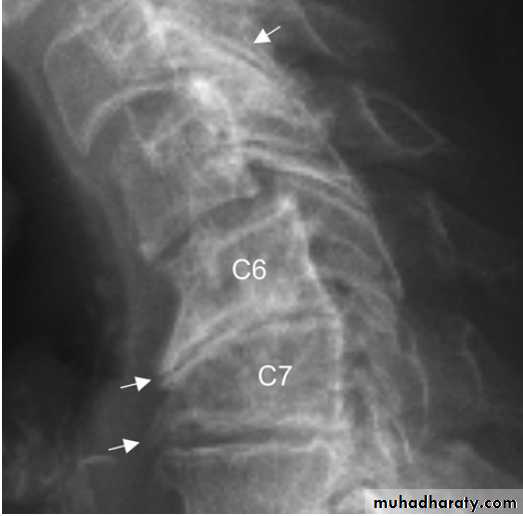

X-ray of spine showing typical changes of

osteoarthritis. Cervical spondylosis showing disc space narrowingbetween C6 and C7, osteophytes at the anterior vertebral body margins (arrows) and osteosclerosis at the apophyseal joints.